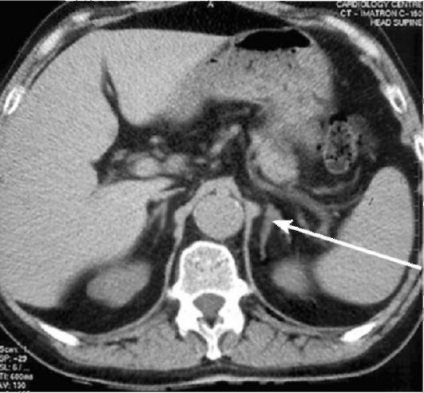

Infarktus a lép be a képen